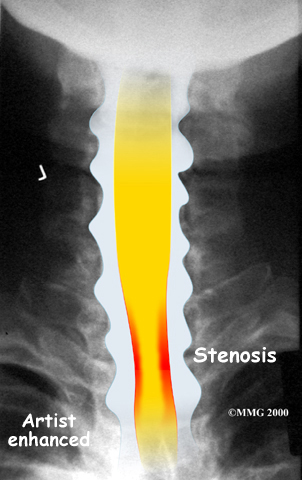

The bony spinal canal normally has more than enough room for the spinal cord. Typically, the canal is just less than ¾ of an inch, or 17-18 millimeters around, which is less than the size of a small bottle cap. Spinal stenosis occurs when the canal narrows to around half an inch, or 13 millimeters or less. When the size drops even further, severe symptoms of myelopathy occur. The symptoms of myelopathy result from the actual pressure against the spinal cord itself as well as the reduced blood supply in the spinal cord as a result of the pressure.

X-rays are used to look for the cause of pressure against the spinal cord. X-ray images can show if degeneration has caused the space between the vertebrae to collapse and may show if a bone spur is pressing against the spinal cord.

If more information is needed, a magnetic resonance imaging (MRI) scan may be ordered. The MRI machine uses magnetic waves rather than X-rays to show the soft tissues of the body. This test gives a clear picture of the spinal cord and can show where it is being squeezed. An MRI machine creates pictures that look like slices of the area your healthcare professional is interested in. This test does not require any special dye or a needle.

A computed tomography (CT) scan may also be ordered. The CT scan is a detailed X-ray that lets doctors see slices of bone tissue. The image can show if bone spurs are protruding into the spinal column and taking up space around the spinal cord.